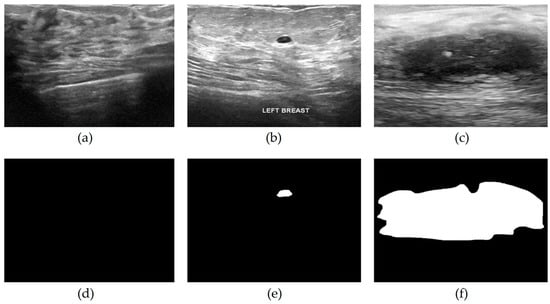

3. Data Collection

Figure 1.

Dataset image samples: (a) normal ultrasound image, (b) benign ultrasound image, (c) malignant ultrasound image, (d) masked image of (a), (e) masked image of (b), (f) masked image of (c).